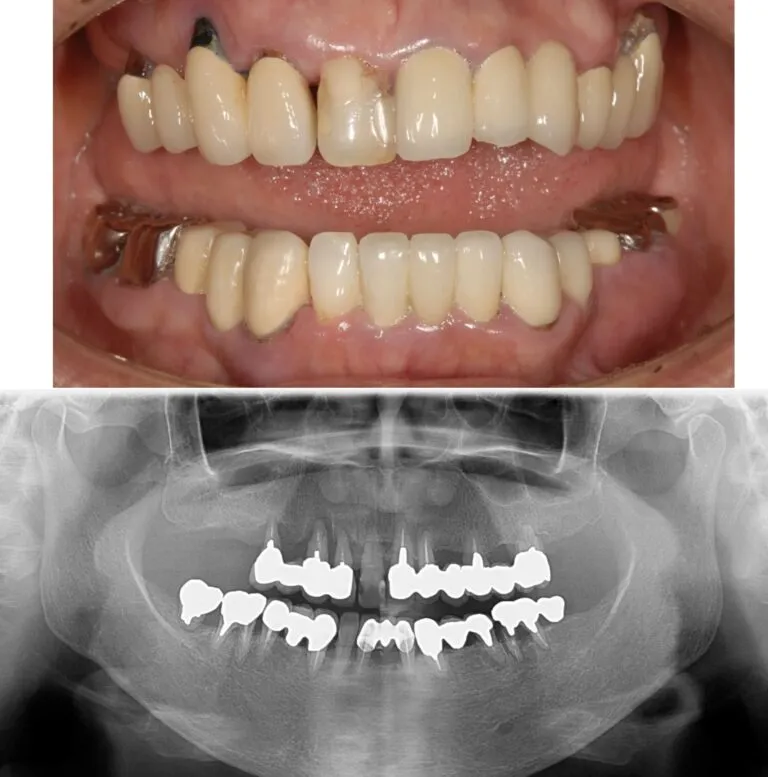

症例4

- 主訴

- 前歯が痛い。全体的な治療を希望

- 治療内容

- インプラント治療、矯正治療、セラミックによる補綴治療

- 治療費

- 400万

- 治療期間

- 2年3ヶ月

- 通院回数

- 70回

before

after